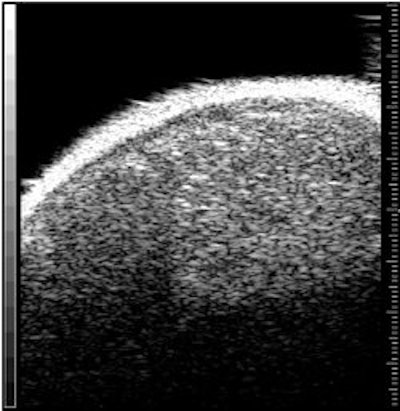

Above, ultrasound image of NHL xenograft done on a 20-MHz transducer at five hours after CHOP chemotherapy. The apoptotic areas correspond to the areas of high-intensity backscatter. Below, corresponding histology image with TUNEL stain. The areas that are stained brown correspond to the apoptotic areas. Images courtesy of Dr. Charles Cho.

The animals were then imaged with 20-MHz spectroscopic ultrasound (VS40B, VisualSonics, Toronto). For the 26 mice that had chemotherapy, imaging was done several times, five to 72 hours after treatment. For the eight mice that had radiotherapy, sonography was performed once, six hours after treatment. Tumor sections were terminal transferase dUTP nick end labeling (TUNEL) stained to confirmed apoptotic cell death.

The authors found a time-dependent increase in backscatter following CHOP chemotherapy, they wrote in their results. The measured high-intensity (10-decibel increase) patch areas on ultrasound were 1.76 mm² at five hours, 0.27 mm² at 12 hours, 2.03 mm² at 24 hours, 2.93 mm² at 48 hours, and 0.12 mm² at 72 hours.

"Image analysis demonstrated a correlation between the size of high-intensity patches on high-frequency ultrasound and immunohistochemical TUNEL staining or apoptotic areas," the group wrote.